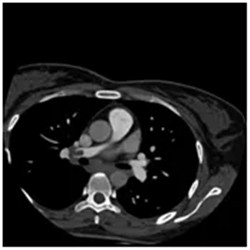

术后患者复查

肺部CTA已有部分再通

之后应用导管至肺动脉造影

发现左肺主干栓塞